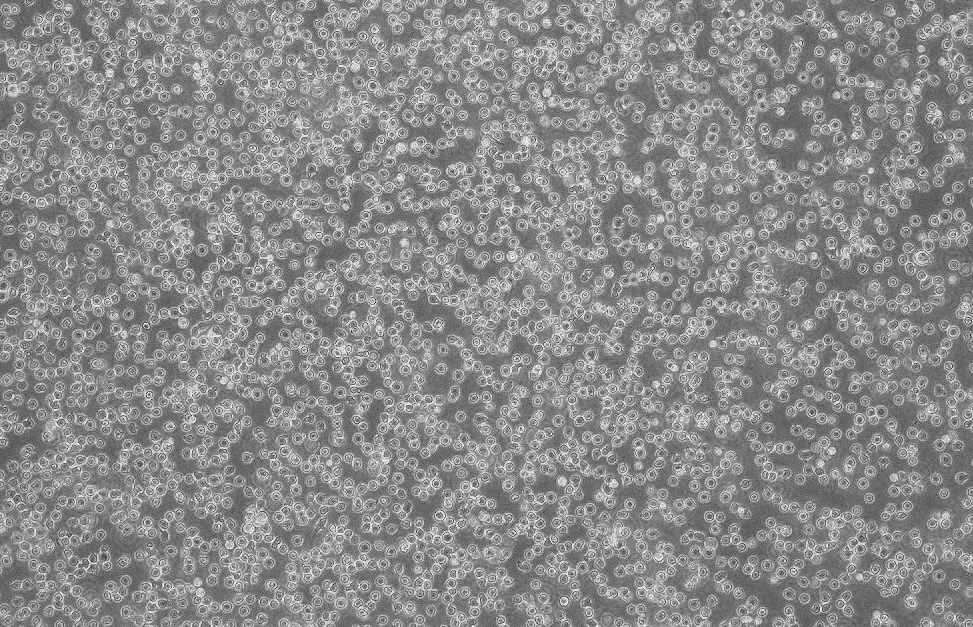

形態(tài) |

淋巴細胞樣 |

生長特征 |

懸浮生長 |